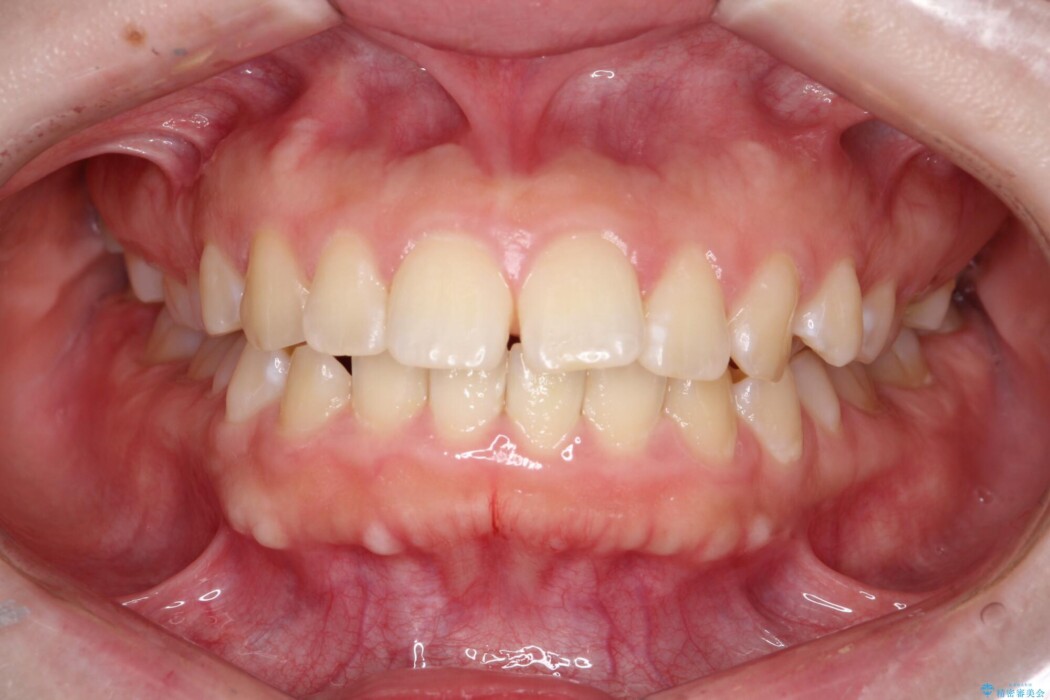

口元の突出感が気になるとご来院された患者様です。

治療計画

矯正検査の結果、前歯が外側に強く倒れ込んでいる「唇側傾斜(しんそくけいしゃ)」が認められ、口元の突出感の原因になっていました。

この傾斜を根本から正し、前歯を十分に後方へ下げるスペースを確保するため、上下左右の4番を抜歯し、目立ちにくい審美ワイヤー装置にて治療を行うこととしました。